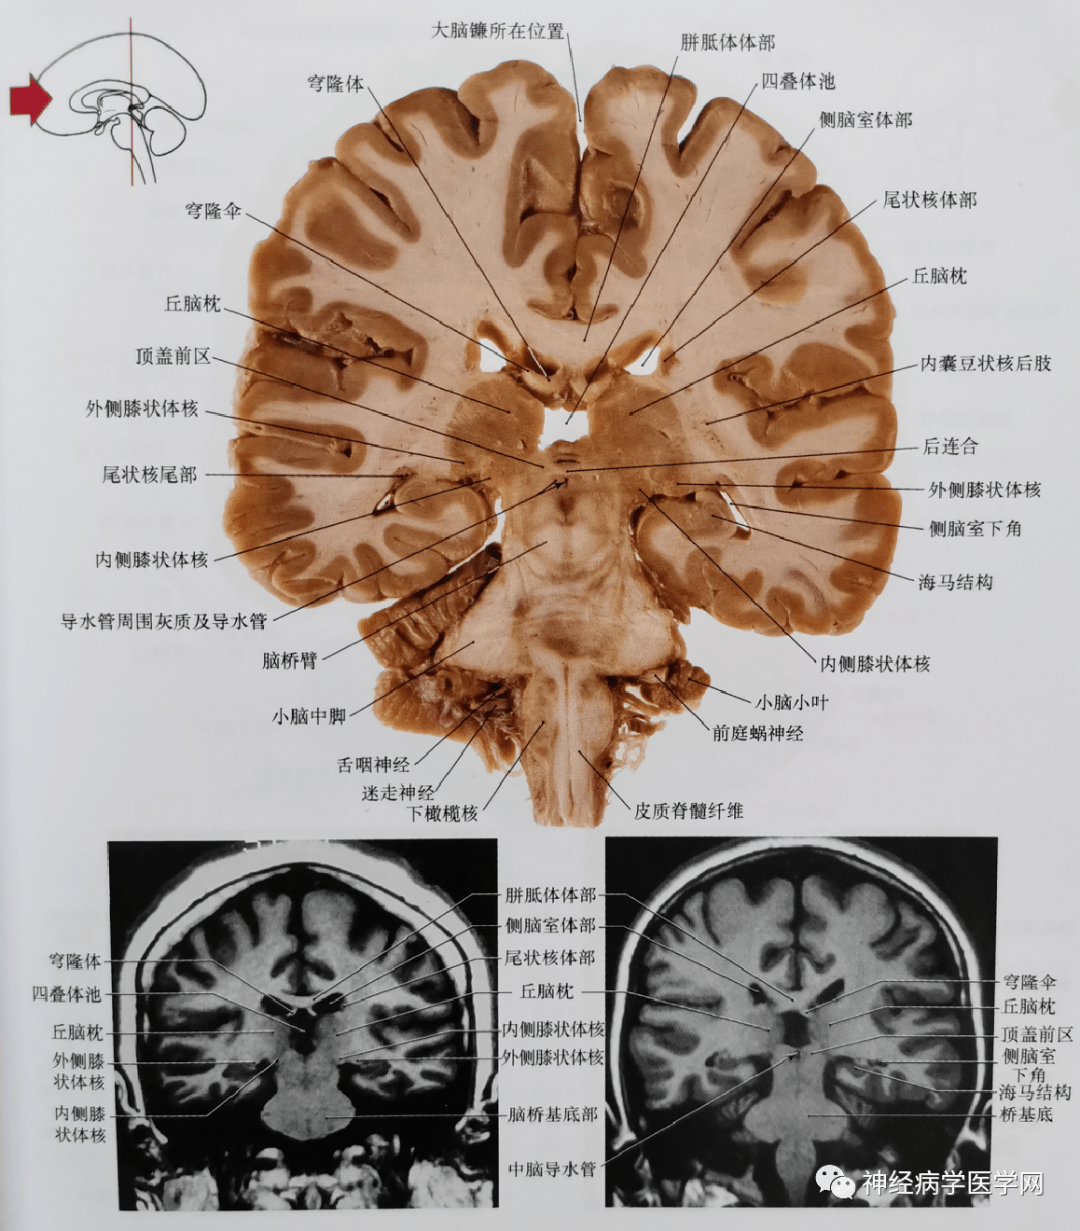

学习借鉴脑的断面解剖

图片尺寸825x832